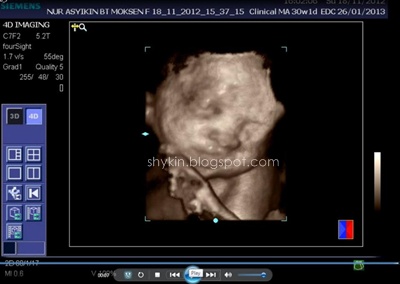

Dulu masa pregnant Fayyadh dan Fathi scan 2D je yang aku tahu. So, Kali ni konon-konon nak merasa la scan 3D. 4D pulak, aku pun ajak la suami pergi buat dekat klinik. Memang teruja la sebab 4D bole dengar sound dan tengok dia gerak-gerak dengan gambar coklat tu. Dah macam ada kat depan mata je baby padahal masih lagi dalam perut. Jakun jugak la haku... ngeh ngeh ngeh.

BTW aku buat dekat Klinik Sofea, Puchong Utama, scan 3d 4d murah la kat situ, RM80 sekali dengan CD. Setakat ini aku rasa kat KL ni tu yang paling murah. Lagi pula, tak payah buat appointment, walk-in terus je.

Proses scan dijalan oleh doktor yang bertugas masa tu. Okeyla jugak, puas hati sebab dia print hampir 10 keping result scan muka tu. Banyakkan??..

Selain scan tengok muka, doktor tu bagi tahu perkembangan graf baby dalam kandungan. Doktor tu cerita la berat baby berapa, jantung dia okey ke tak, tumbesaran dia normal ke tak, air ketuban cukup ke tak, dan yang paling penting dia bagitahu dan 'tunjuk' sekali jantina baby. (* excited kan ? )

Jom view hasil 4dscannya. Yang ni aku printscreen dari VCD yang klinik tu bagi.

Insyallah, kami bakal menimang cahayamata PEREMPUAN. kalau ikut scan tula..

sebenarnya tak kisah pun jantina apa, tapi puas hati sebab dapat tahu yang dia sihat kat dalam kandungan.